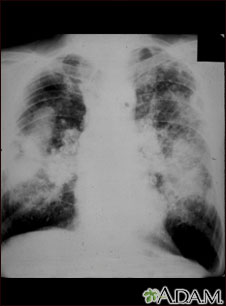

Esta imagen muestra la neumoconiosis complicada del minero. En la parte superior y media de ambos pulmones, hay áreas difusas, masivas y claras que corren paralelas y están superpuestas a un fondo de pequeñas áreas claras, difusas y difíciles de distinguir, que cubren ambos pulmones. Las enfermedades que pueden explicar estos hallazgos en una radiografía son la neumoconiosis complicada del minero (NCM), silicotuberculosis, y cáncer metastásico de pulmón.